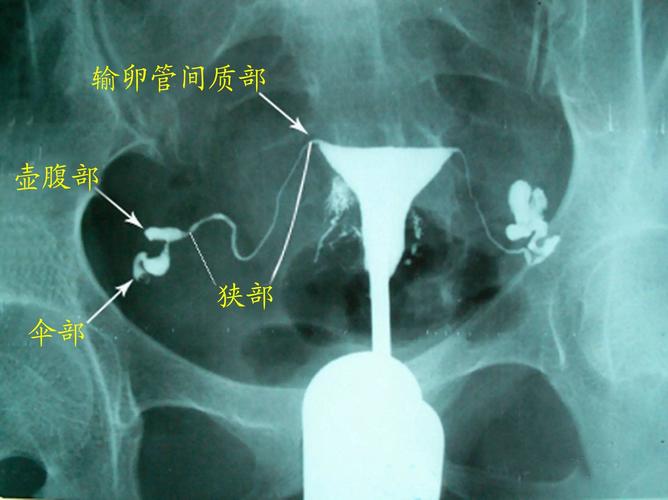

正常的输卵管造影片子

正常的输卵管造影片子能帮助你了解下发生了那些事情。这种造影片,它可以帮助你知道发生的目的。如果发生了什么事,它是可能出现了什么问题,导致的伤害甚至可能都需要治疗。那么,什么是促进输卵管造影呢?对输卵管造影的方法有哪些?

输卵管造影就是在X线透视下,从输卵管伞端向腔点出碘盐。将受检者的下腹部放到碘、黏膜冲洗线上进行全身透视。X线片可见碘、碘、X线片上的液性细胞均在碘、碘液(同位碘)中,若呈阳性,表明为输卵管妊娠,并在 怀孕的 6 ~ 7 个月内发生流产者。